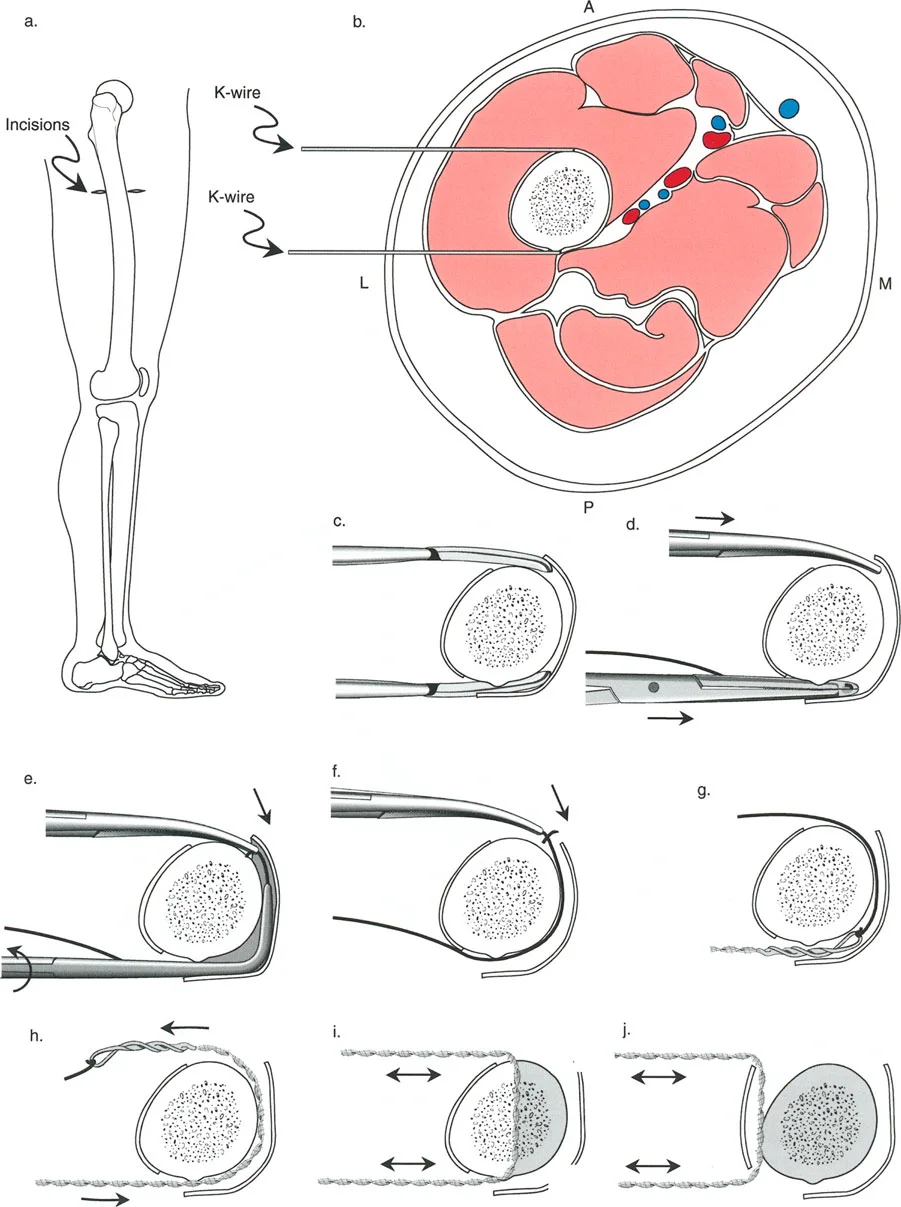

إتقان معدلات الشد: قاعدة المثلثات المتشابهة

القاعدة الذهبية البيولوجية لتوليد العظم بالشد، التي وضعها إليزاروف بعد عقود من التجارب على الحيوانات والبشر، هي معدل شد يبلغ 1 ملم يوميًا. يتم تقسيم هذا عادة إلى زيادات قدرها 0.25 ملم كل 6 ساعات لمحاكاة النمو المستمر للوحة النمو.

ومع ذلك، فإن الخطأ الشائع، الذي قد يكون كارثيًا أحيانًا للجراحين المبتدئين، هو سوء فهم أين يجب أن يحدث هذا الـ 1 ملم يوميًا.

معدل 1 ملم/يوم ينطبق بشكل صارم على القشرة المقعرة للعظم في موقع قطع العظم (الحافة الأمامية للإسفين المفتوح). نظرًا لأن الجهاز (قضيب الشد أو دعامة TSF) يقع على مسافة من العظم، خارج غلاف الأنسجة الرخوة، فإنه يتحرك على طول قوس أكبر بكثير. إذا وجهت المريض لشد القضيب بمعدل 1 ملم يوميًا، فإن العظم الفعلي سيُشد بجزء ضئيل من هذا المعدل، مما يؤدي إلى التصلب المبكر لموقع قطع العظم.

حساب معدل الشد الحقيقي

لحساب المعدل الصحيح للشد عند المفصلة، نستخدم قاعدة المثلثات المتشابهة، والتي تعتمد أساسًا على القاعدة الهندسية للدوائر متحدة